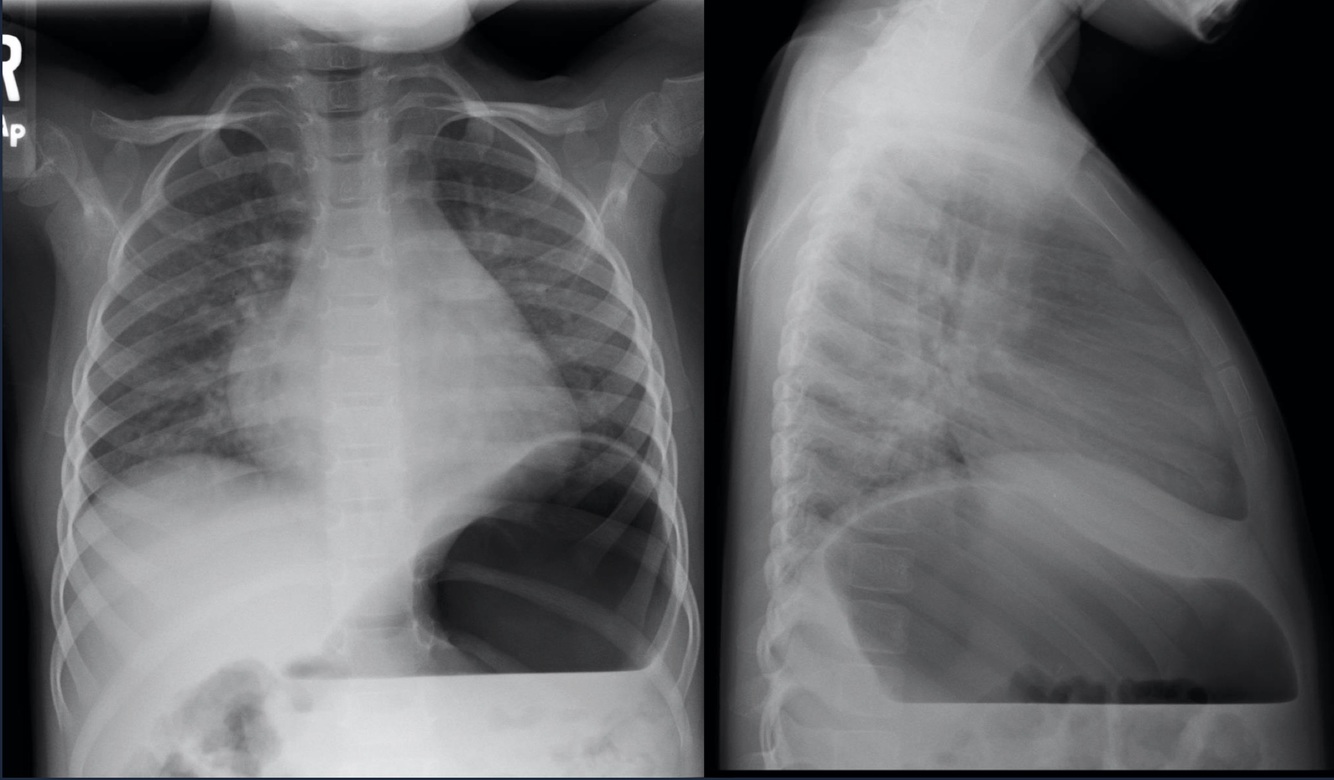

Lateral View

By convention, beam on the right, detector on the left.

Can see b/l oblique fissures and horizontal fissure on the right.